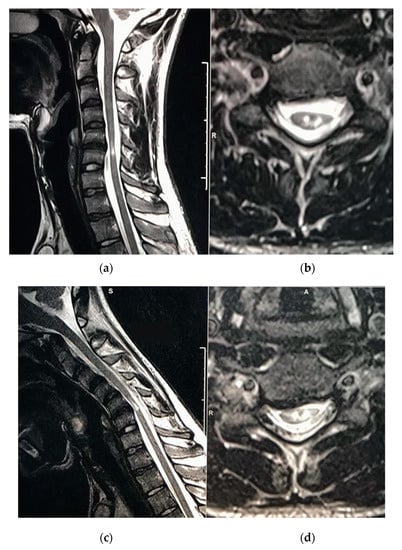

Snake-Eye Myelopathy and Surgical Prognosis: Case Series and Systematic Literature Review

3.2. Case Series